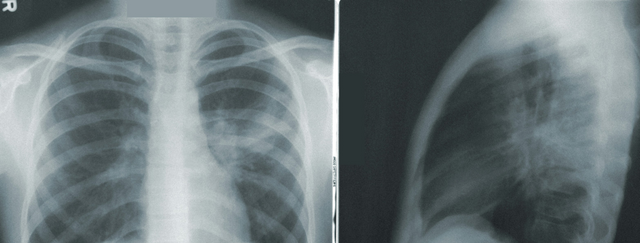

В отличие от других методов вентиляции, PEEP эффективно предотвращает коллапс альвеол, обеспечивая их открытость даже при сниженном объеме дыхательных движений. Особенно важно применение этого метода при лечении острой респираторной недостаточности, например, при остром респираторном дистресс-синдроме (ARDS), где поддержание открытости альвеол является критически необходимым для обеспечения адекватного газообмена.

• Ателектаз (коллапс легкого или его части)

• Пациент с ARDS: При остром респираторном дистресс-синдроме применение PEEP является критически важным для поддержания альвеол в открытом состоянии, что препятствует их коллапсу и улучшает оксигенацию. Такой подход снижает смертность и улучшает прогнозы для пациентов, обеспечивая более стабильный газообмен и уменьшая риск развития дополнительных осложнений.